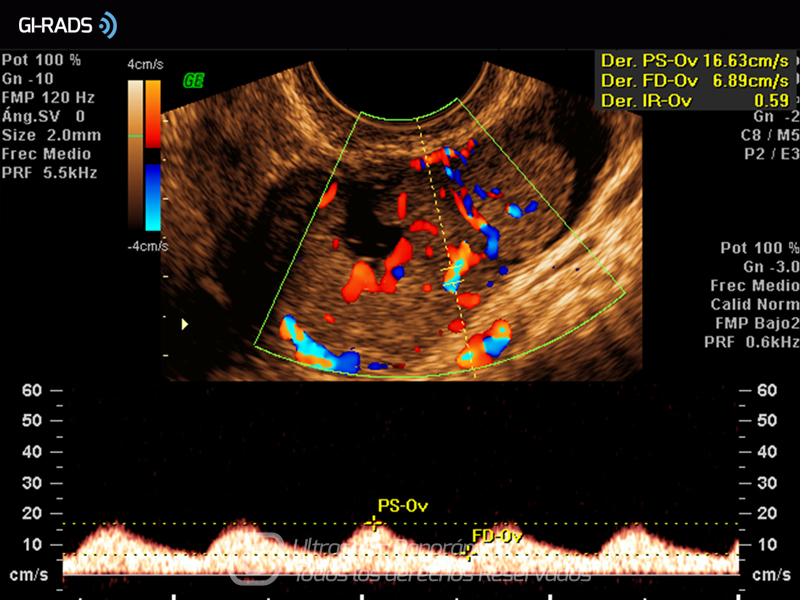

Cáncer Anexial – Flujo Abundante

• Cáncer Anexial – Flujo Abundante